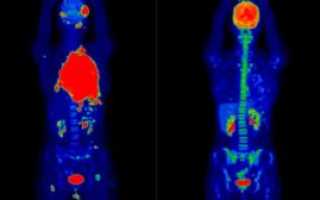

Высокие уровни инсулина вследствие недавнего употребления углеводистой пищи, либо после его экзогенного введения, могут привести к значительному захвату изотопа мышечной тканью, что ухудшает качество исследования (Рисунок 1).

Пациенту следует избегать повышенной физической нагрузки за день до исследования, а после инъекции ФДГ следует расслабиться, прекратить разговаривать, жевать, необходимо избегать гипервентиляции – для того, чтобы минимизировать физиологический захват 18-ФДГ мышечной тканью.

На данном снимке видны метастазы опухоли в печень, визуализируются даже небольшие по размерам узлы на периферии.